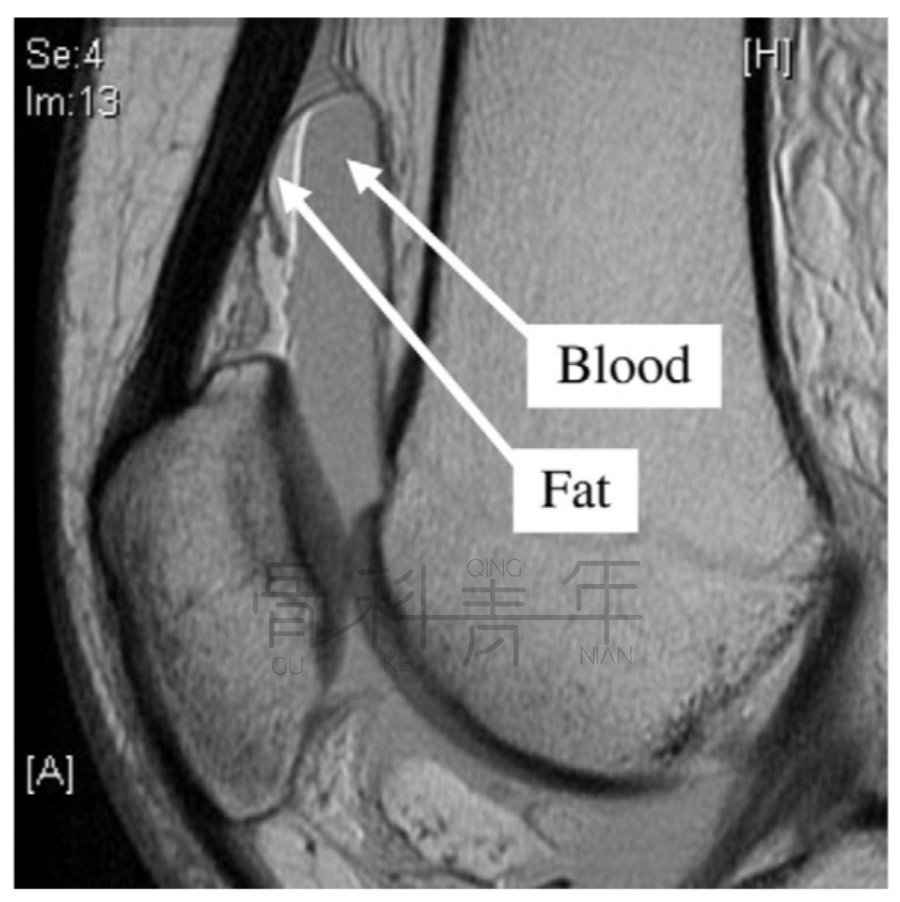

病例2 一例左膝外伤患者。在MR横断与矢状位上均可见明显液体分层(见箭头所示)。